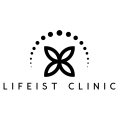

Diş İmplantları ve Restorasyonları

Tek çenedeki tüm dişleri sadece 4 veya 6 titanium implant üzerine sabit zirkonyum/akrilik köprü